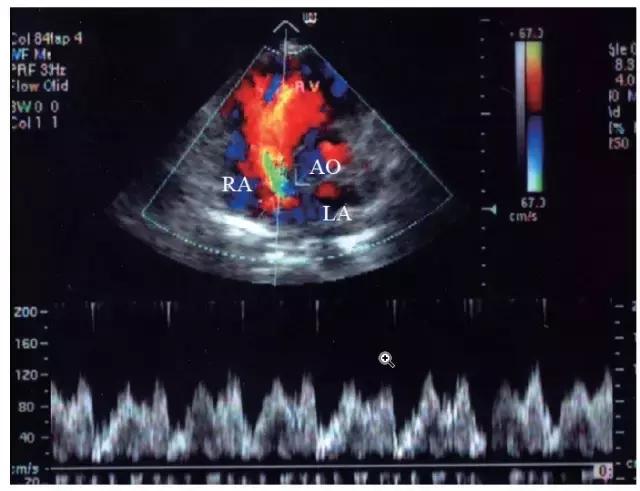

正常人左心房的压力为0.53 ~ 1.07kPa(4 ~ 8mmHg),右心房的压力为0 ~ 0.66kPa(0 ~ 5mmHg)。房间隔缺损时,过隔血流由压力较高的左心房流向压力较低的右心房,但由于两个心房之间的压力阶差不大,脉冲多普勒在房间隔缺损右心房面取样为低速连续性血流频谱,以舒张期为主,速度很少超1.2m/s。